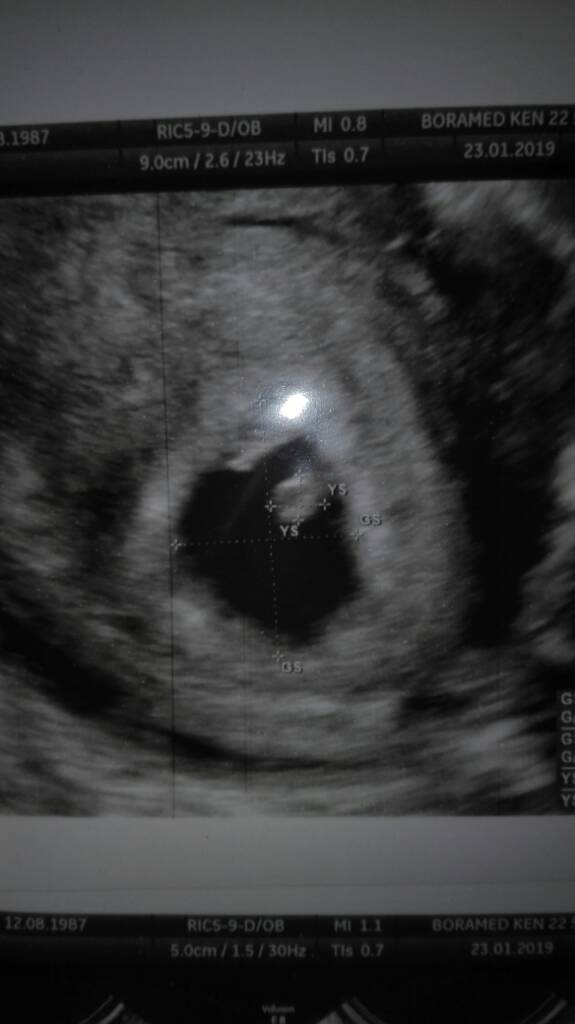

Takie ulozenie to na dziewczynkę czy chlopca ?Zobacz załącznik 936290

Kurcze, właśnie spojrzalam i syn byl po drugiej stronie niz teraz zarodek. To juz sama nie wiem.Stawiam chłopca. Moi podobnie byli ułożeni.